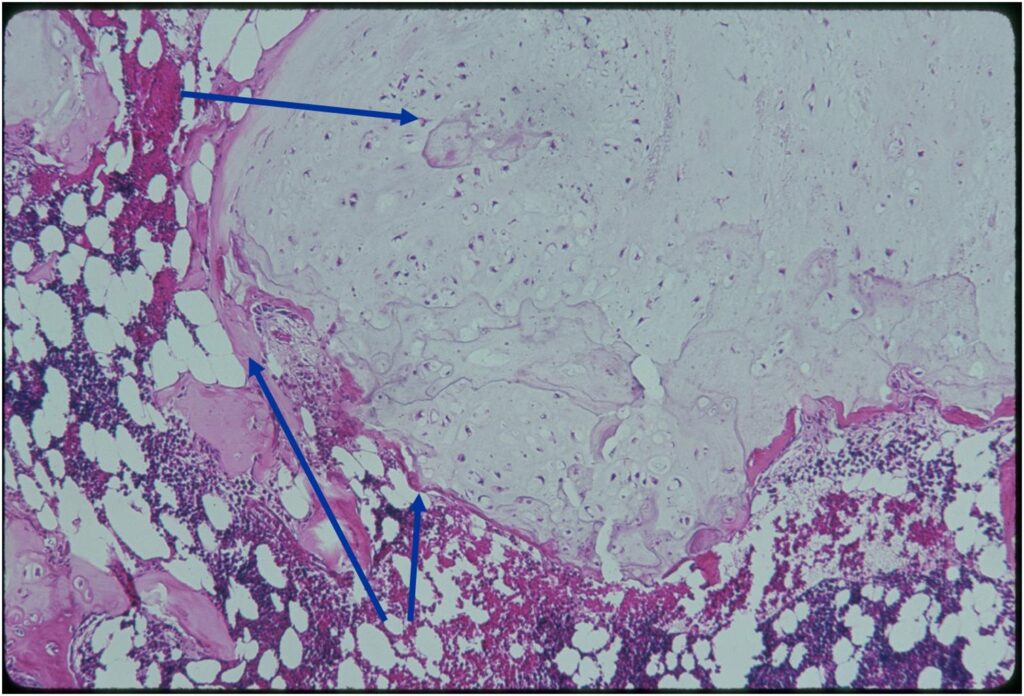

- Enchondromas are well defined lesions with cartilage arranged in lobules that are separated by fibrovascular septa

- Enchondral ossification may occur around periphery of lobules and when calcified appear as “Rings and Arcs” on X-rays

- Cells are in lacunae and have small dark nuclei

- Low cell count, cells appear bland with few chondrocytes and are similar size and shape

- Although some enchondromas may have areas that are hypercellular and may have two or three cells within a lacunae

- No entrapment or destruction of trabeculae